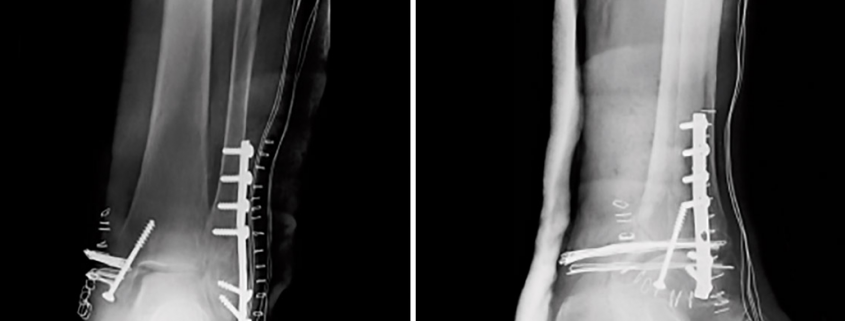

Para saber cuánto paga la ART por una fractura de tibia y/o peroné, primero hay que determinar si la lesión compromete la tibia, el peroné o ambos huesos. Según eso, se establecerá el porcentaje de incapacidad y el monto de indemnización correspondiente 💰.

También se evalúa si los huesos consolidaron correctamente o si hubo complicaciones como afectación nerviosa. Cada uno de estos factores puede impactar notablemente en el resultado final del reclamo ante la ART.

Al momento de iniciar el trámite ante la Superintendencia de Riesgos del Trabajo (SRT) para que se determine el porcentaje de incapacidad, los médicos de las comisiones evaluadoras aplican el Baremo del Decreto 659/96. Esta tabla establece los porcentajes orientativos de incapacidad según el tipo de lesión sufrida.

Además del tipo de fractura, se tienen en cuenta otros factores importantes como:

🔹 La zona específica del hueso fracturado

🔹 La consolidación ósea (si los huesos sanaron correctamente)

🔹 La presencia de pseudoartrosis (cuando los extremos del hueso no logran unirse adecuadamente)

🔹 La afectación de nervios periféricos, como el nervio ciático poplíteo externo, peróneo o tibial

📌 De acuerdo con el Baremo oficial, el porcentaje de incapacidad por fractura de tibia y/o peroné puede variar entre un 5% y un 20%, dependiendo del tipo, la ubicación exacta, la evolución clínica y la rehabilitación lograda. A eso debe sumarse la incapacidad psicológica, el daño neurológico, los factores de poderación, etc.